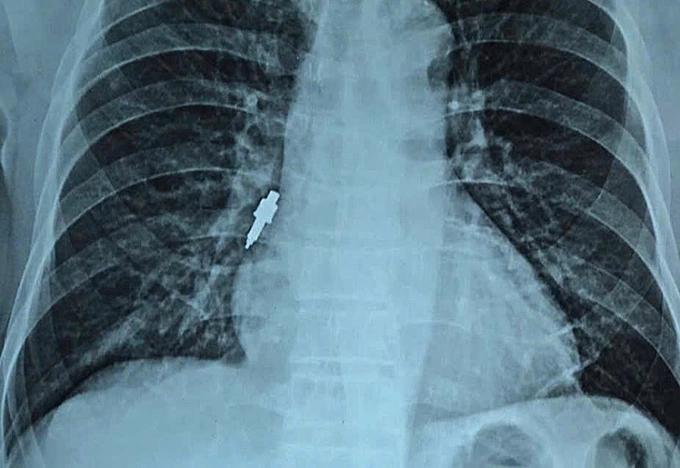

Dụng cụ nha khoa rơi vào đường thở sau khi làm răng

Hà Nội- Sau hai tuần cấy ghép implant tại phòng khám tư, người đàn ông 78 tuổi ho dữ dội, bác sĩ Bệnh viện Hữu Nghị phát hiện một dụng cụ kim loại kẹt sâu trong phế quản.